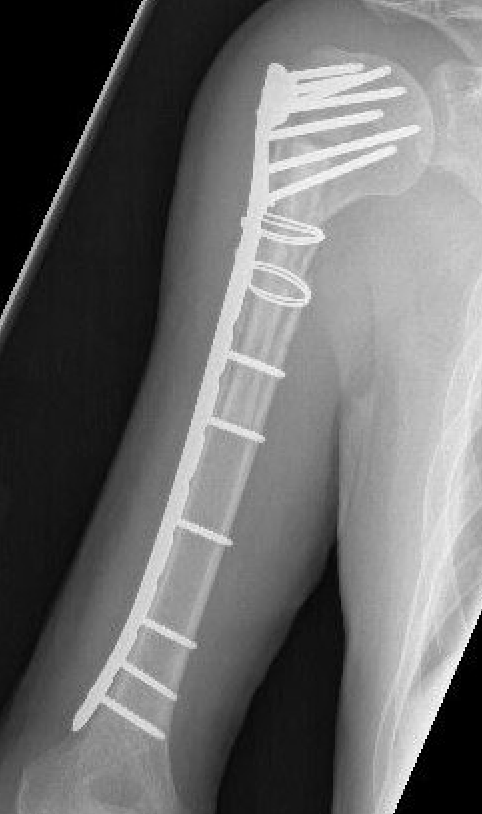

Anterior plating with narrow 4.5 mm LCP

Lateral plating with long proximal humerus plate

Jeong et al. BMC Musculoskeletal Disorders

- 18 patients treated with narrow LCP (anterior)

- 17 patients treated with long Philos plate (lateral)

- 2 metal failures in the Philos plate group requiring revision to LCP

Narrow LCP plate

Precontour narrow LCP plate

- subtle convex curve proximally

- subtle concave curve distally

- 10 - 15 degrees internally rotated